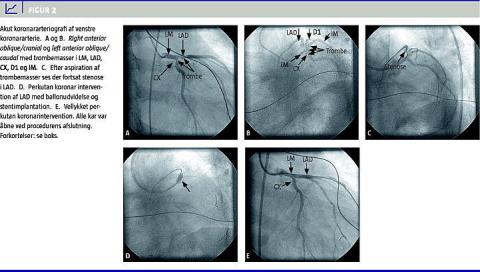

Akut koronararteriografi (KAG) viste trombemasser i hovedstammen, left anterior descending artery (LAD) og ramus circumflexus, diagonalgrenen og intermediærgrenen. Efter aspiration af trombemasserne var der stadig mistanke om en fikseret stenose proksimalt i LAD. Derfor blev der i umiddelbar forlængelse af undersøgelsen foretaget primær perkutan koronarintervention med indsættelse af en drug-eluting stent i LAD. Alle kar var åbne ved procedurens afslutning (Figur 2 ). Behandling med glykoprotein IIb/IIIa-hæmmeren abciximab blev opstartet under proceduren. De biokemiske test viste forhøjede serumværdier af kreatininkinase-myocardial band -masse (CKMB 9,2-236 mikrogram/l) og troponin-T (TNT 0,20-5,33 mikrogram/l). Totalkolesterol blev målt til 3,5 mmol/l. Patienten blev efterbehandlet med 75 mg clopidogrel i 12 måneder og derefter sat i behandling med 75 mg acetylsalicylsyre daglig resten af livet. Ekkokardiografi viste global hypokinesi, der dog var mest udtalt anteroseptalt, og en estimeret uddrivningsfraktion (EF) på 20%.